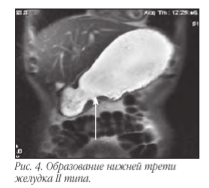

Снова оценивается положение осей желудка, и срезы выставляются строго по осям, используя Т2ВИ. При нахождении подозрительного участка стенки желудка устанавливаются срезы толщиной до 3 мм параллельно и перпендикулярно патологической зоне, что позволяет определить протяженность поражения стенки, ее толщину, глубину поражения, наличие изъязвлений и нарушение целостности серозного слоя. В дополнение к Т2ВИ используются программы Т1 TRUFI и DWI.

В связи с тем, что визуализировать достоверно все слои стенки желудка чаще всего не представляется возможным, то критериями ее поражения являются степень утолщения и протяженности изменений. При поражении всех слоев и распространении процесса за пределы серозы основными МР-признаками следует считать нечеткость и размытость наружного контура стенки желудка, снижение сигнала от перигастральной жировой клетчатки. В современной лучевой диагностике МРТ применяется для определения стадии по N и M стадиям, используя TNM классификацию. Мы в своей работе используем классификацию Японской ассоциации по раку желудка. В основе классификации JGCA (1998) лежит анатомический принцип. В отличие от принципов JGCA, классификация UICC (Международного противоракового Союза 2002) рассматривает лишь количественное поражение регионарных лимфатических узлов вне зависимости от их локализации.

Т1: опухоль поражает слизистый слой и/ или подслизистый слои.

Т2: опухоль поражает собственно слизистый или субсерозный слой.

Т3: опухоль пенетрирует серозный слой.

Т4: опухоль инвазирует окружающие ткани.

Метастатическое поражение лимфоузлов, печени и брюшины - N, H и P.Основными признаками поражения стенок желудка являются: утолщение стенки более 5 мм, неровность и бугристость контуров, изменение МР-сигнала от образования, распространение за пределы стенки.